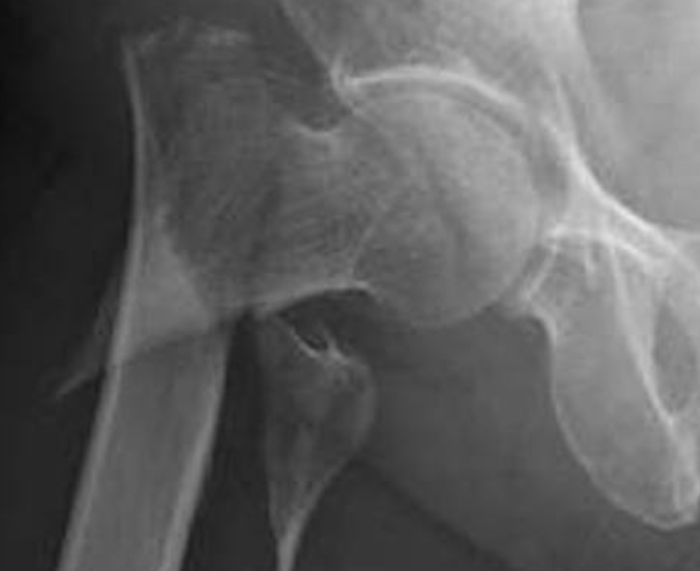

③ 大腿骨の骨折

普通であれば問題ない軽い転倒。

骨粗鬆症の方は大きな骨折に

繋がってしまいます…

大腿骨という足の骨が

写真のようにバキッと

折れてしまうことがあります。

こうなると歩くことができず

ほぼ確実に手術が必要になります。

手術しても歩く能力は落ちて

杖をつくことが多くなります。